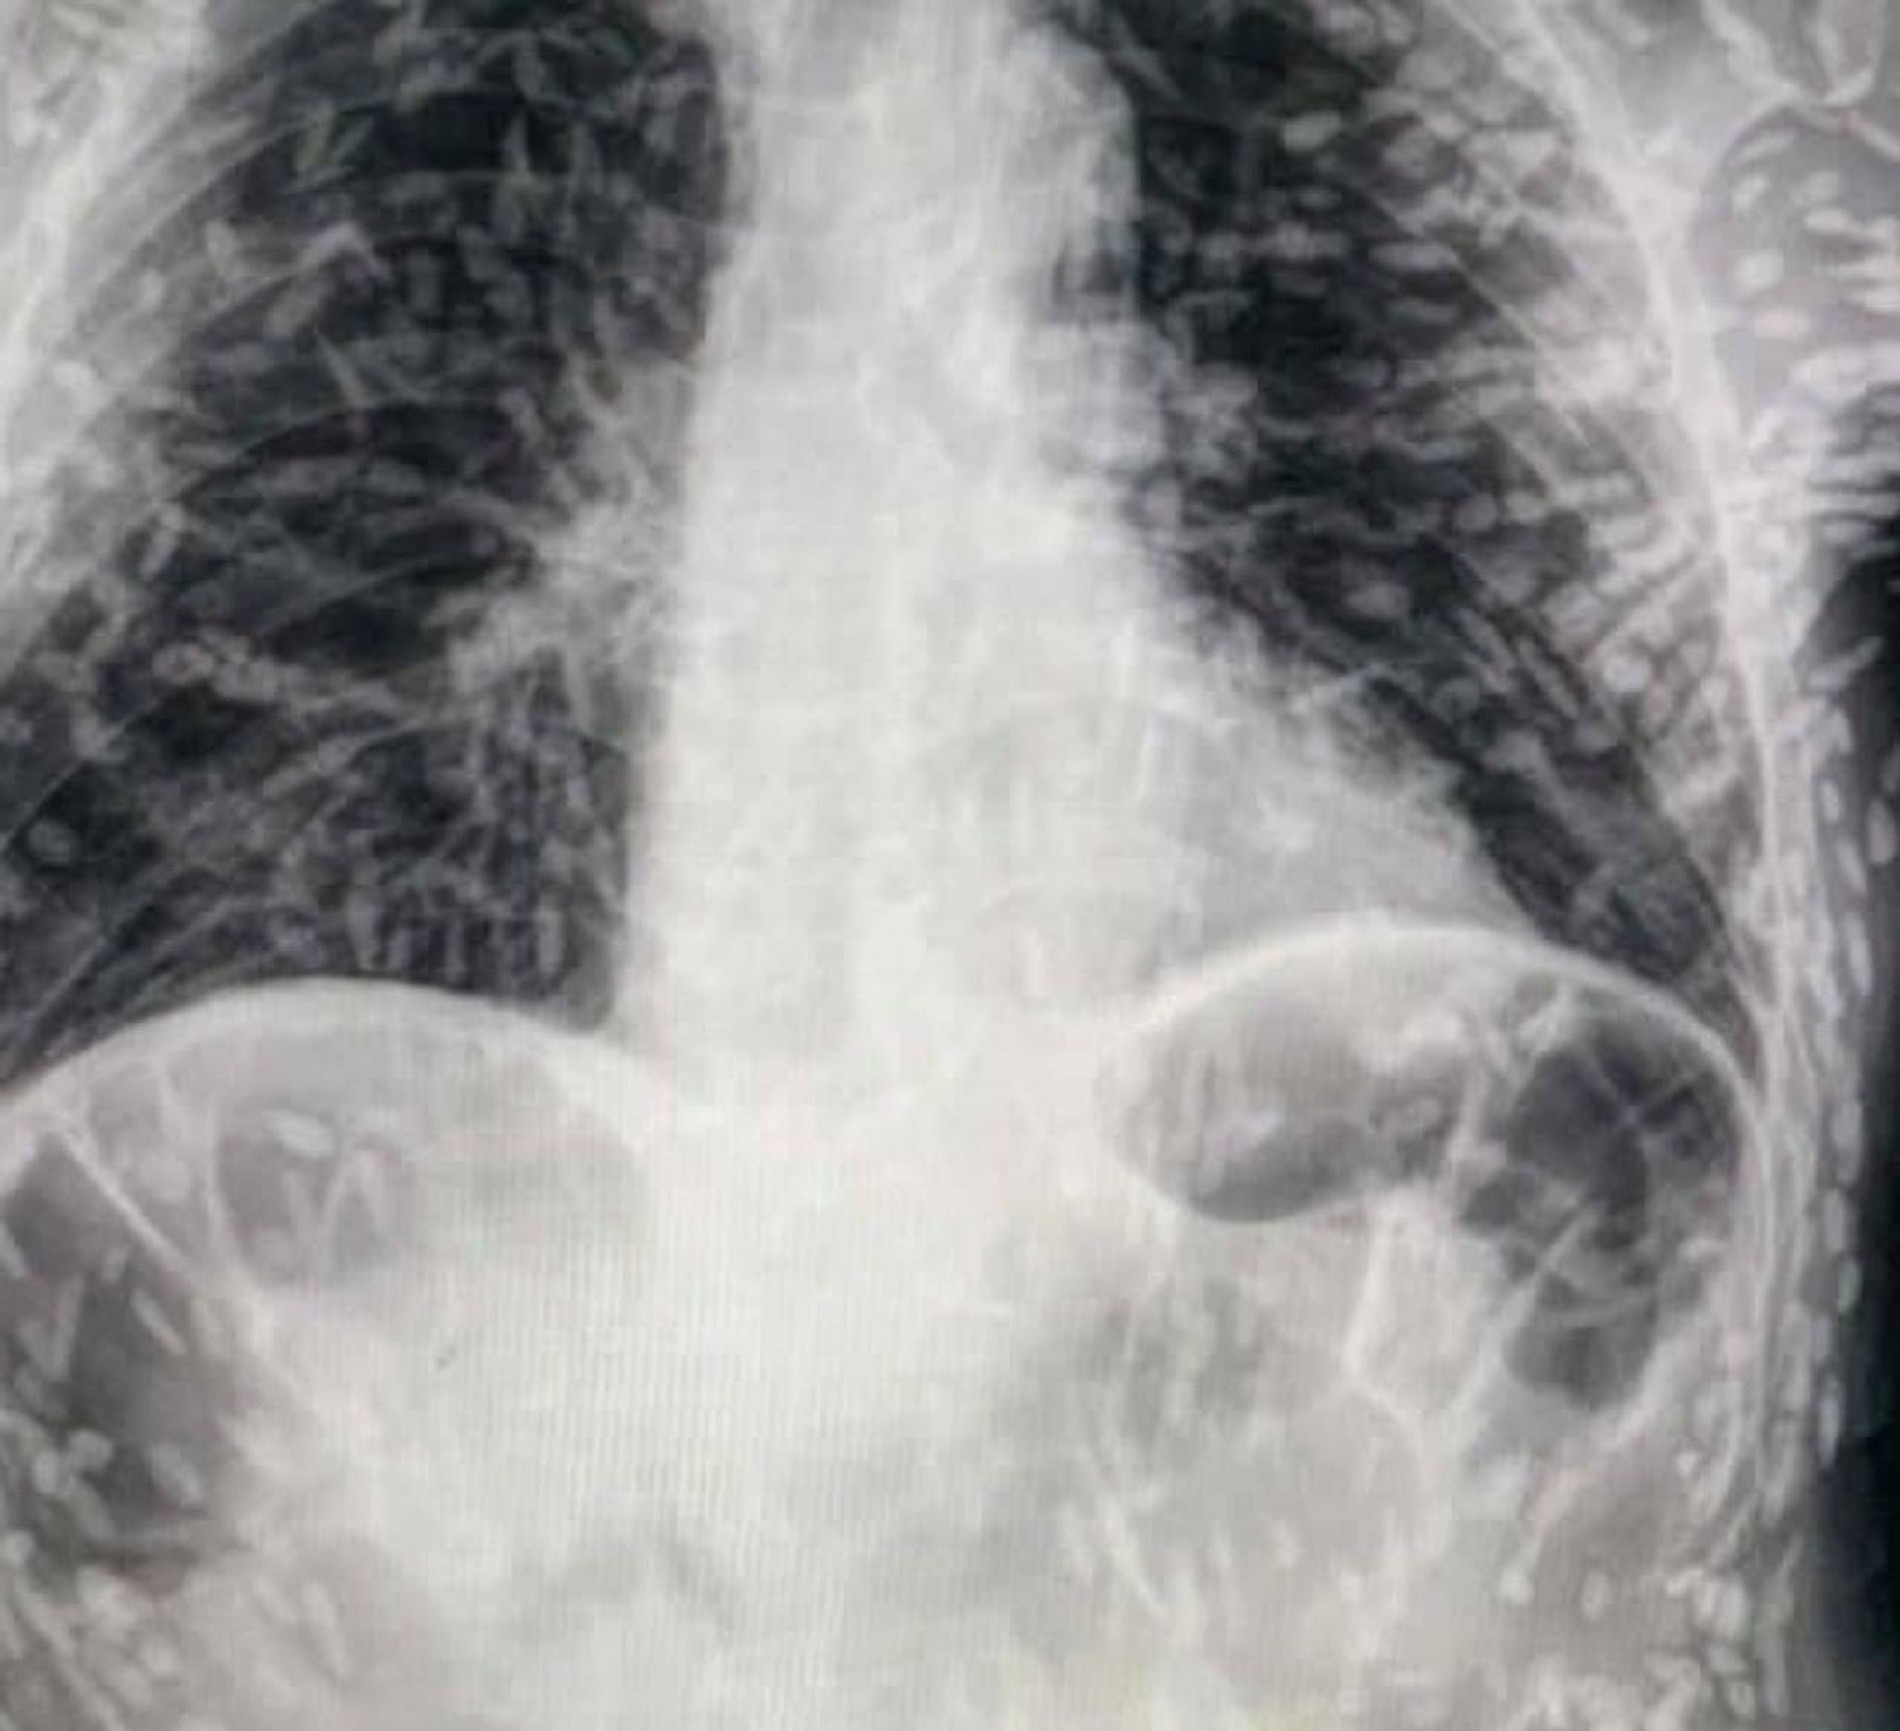

Ученые поделились рентгеном человека, тело которого было усеяно яйцами опасного паразита: ужасающее фото

С помощью одного-единственного рентгеновского снимка бразильский врач привел в ужас и подарил вечную паранойю миллионам пользователей Twitter. Доктор Витор Борин де Соуза, практикующий в Hospital das Clínicas бразильского города Ботукату, штат Сан-Паулу, показал, как выглядит запущенный случай цистицеркоза. При этом заболевании яйца гельминта через немытые руки попадают в желудок и кишечник, где плотная оболочка яиц растворяется и освободившиеся зародыши по кровеносным сосудам разносятся по тканям и органам человека. Собственно, многочисленные белые пятна на животе и руках пациента и есть те самые зародыши, личинки ленточного червя, объяснил де Соуза. Пациент обратился в больницу из-за непроходящего кашля и головных болей. К счастью, эти личинки не представляют опасности, потому как не выживают в таких условиях. Однако если процесс затронет мозг или глаза, последствия могут быть критичными. Из-за нейроцистициркоза погибает около 50 тысяч человек в год, а еще он является самой распространенной причиной приобретенной эпилепсии в мире.

Запущенный цистицеркоз подобно тому, что продемонстрировал доктор де Соуза, возникает, как правило, у пациентов с ослабленным иммунитетом. И хотя людям с хорошей иммунной системой вряд ли грозят подобные ужасы, подозреваем, все, кто видел этот снимок, больше никогда в жизни не притронутся к продуктам грязными руками.